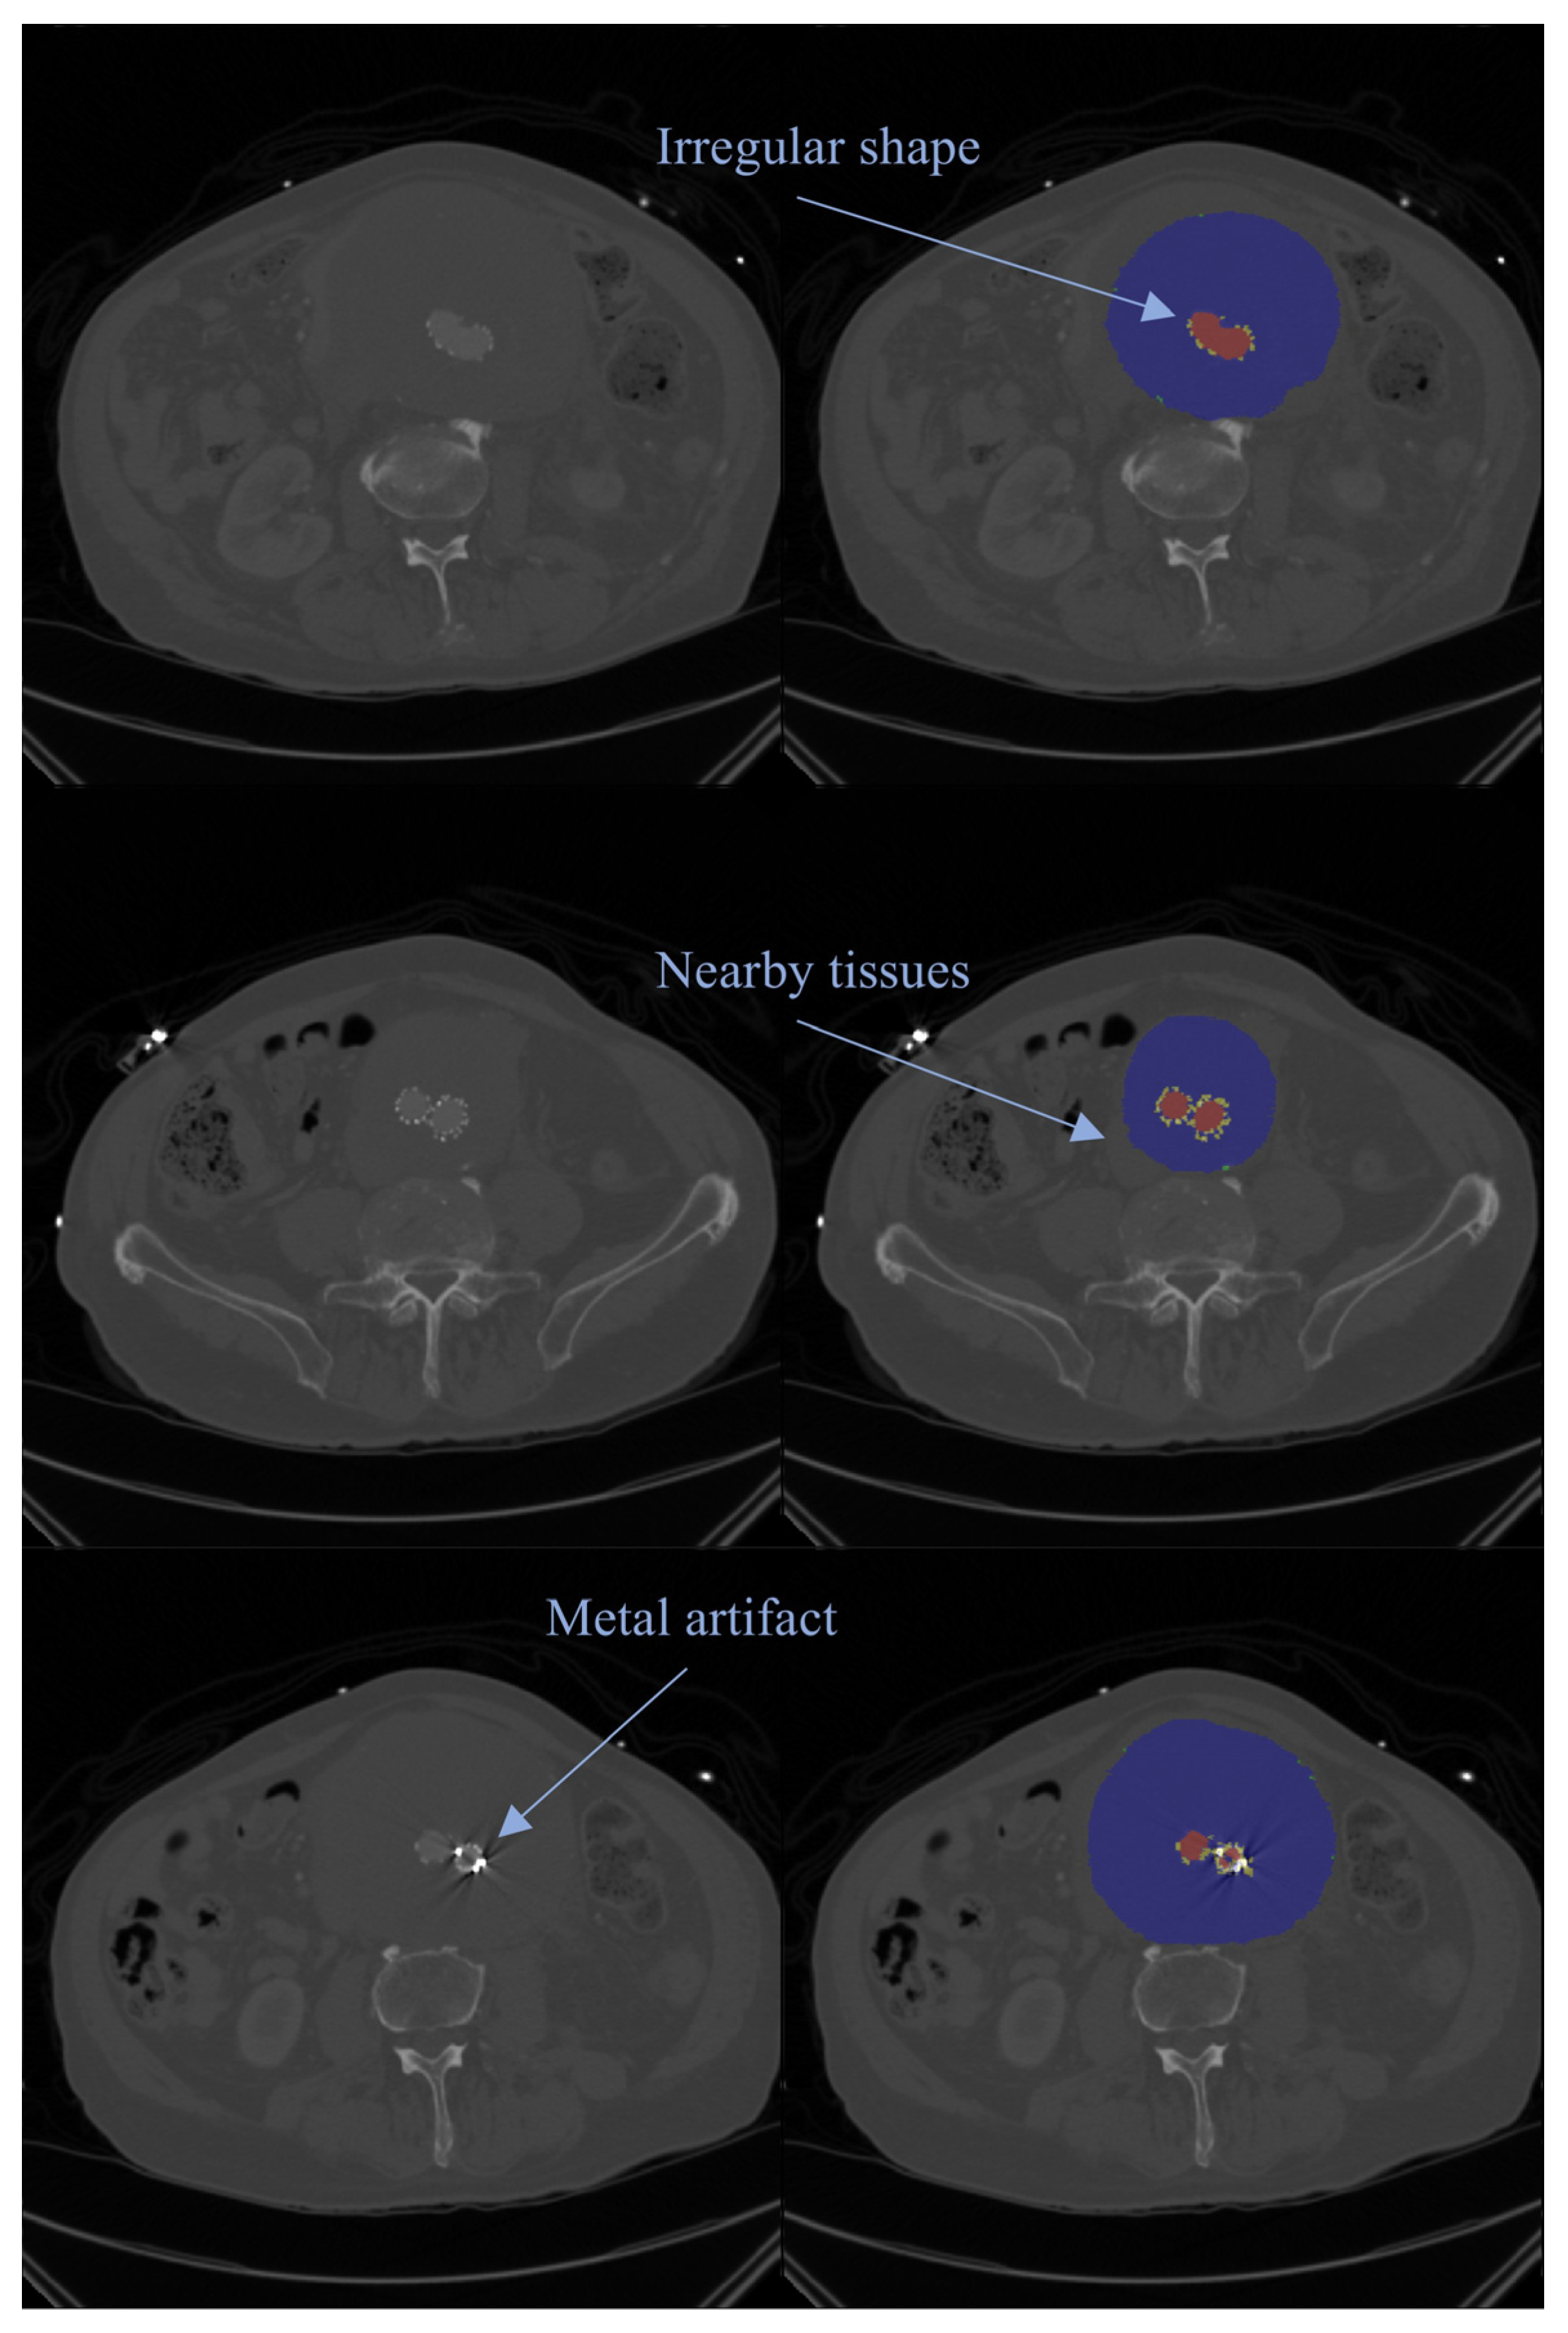

- Barrett, J.F.; Keat, N. Artifacts in CT: Recognition and Avoidance. Radiographics 2004, 24, 1679–1691. [Google Scholar] [CrossRef]

- Boas, F.E.; Fleischmann, D. CT Artifacts: Causes and Reduction Techniques. Imaging Med. 2012, 4, 229–240. [Google Scholar] [CrossRef]